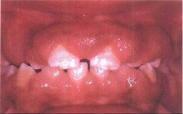

• 藥物性牙齦增生

628健康網為您分享有關藥物性牙齦增生的癥狀,藥物性牙齦增生的治療方法,藥物性牙齦增生的預防知識,藥物性牙齦增生的癥狀...